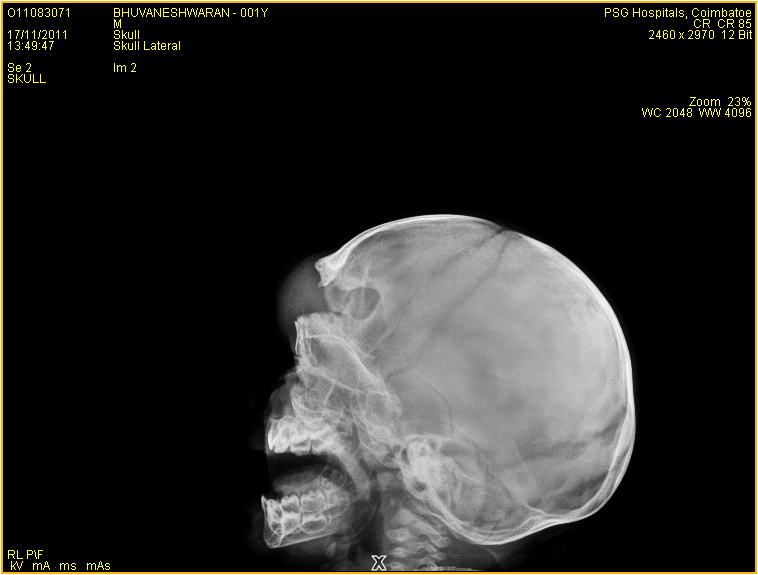

A Rare Case of Right Frontal and Ethmoidal Bony Deformity With Schizencephaly

Agenesis of skull bones, schizencephalyAbstract